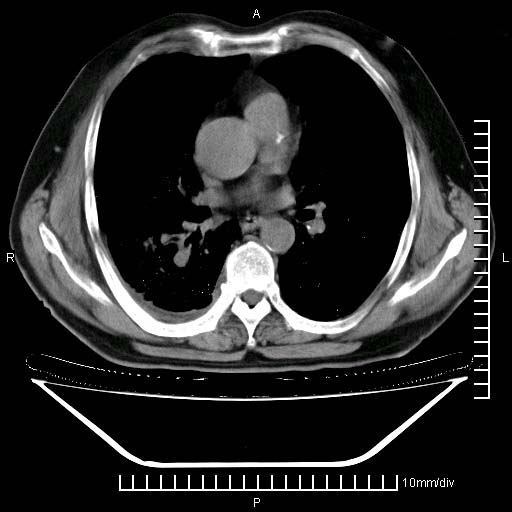

标题: CT24043:胸部增强:男性,60岁 [打印本页]

标题: CT24043:胸部增强:男性,60岁

既往肺结核,近10几天,咳嗽,咳痰,右侧胸痛,疼痛较明显,右上肺斑块考虑结核灶胸膜粘连,增强,可惜动脉期没有定好,未见强化,可延迟4分后又见较明显强化,中心见低密度影,如果说结核是边缘强化,可这个灶强化的面积挺大的,让人很挠头。

动脉期